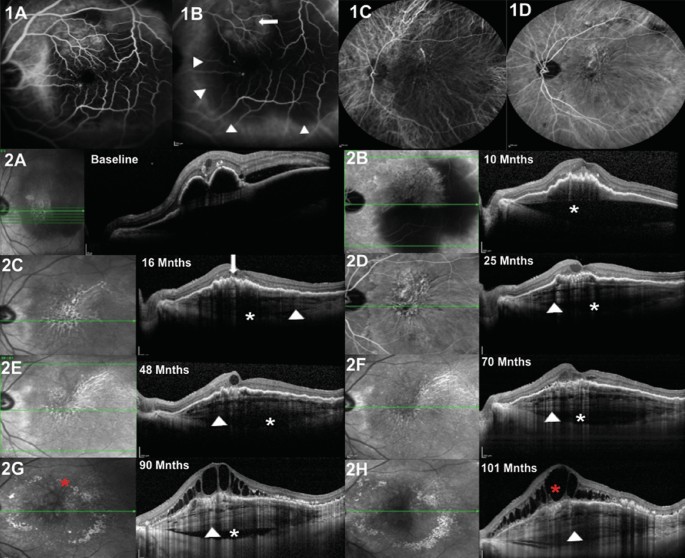

Left eye of an 83-year-old male with age-related macular degeneration (nAMD) and multilayered pigment epithelial detachment secondary to chronic anti-vascular endothelial growth factor (anti-VEGF) therapy (s-MLPED). Baseline angiography shows a neovascular network (arrow) with large pigment epithelial detachment (PED; arrowheads) (B). An increase in the size of the network was noted on follow-up indocyanine green angiography (ICGA; D). Serial cross-sectional optical coherence tomography (OCT) over a period of 101 months shows an increase in multilayering (arrowhead) with a persistent choroidal cleft (white*) and irregular crenated retinal pigment epithelium (RPE; arrow; A–H). The onset of Multilayering was seen at 16 months after starting anti-VEGF therapy (C) which continued to increase during treatment (D–H). Persistent intraretinal fluid and exudation (red*) can be seen late during follow up (G, H).

Intraretinal cleft was noted in 2 eyes, one each in the DN-MLPED and s-MLPED group (Tables 2, 3), and showed a decrease in DN-MLPED eye during treatment. Recurring and disappearing choroidal clefts were seen in 7 eyes (DN-MLPED: 3 eyes; s-MLPED: 4 eyes) (Tables 2, 3). Subretinal hyperreflective material (SHRM) was noticed in 7 eyes (DN-MLPED: 3 eyes; s-MLPED: 4 eyes), 4 eyes demonstrated increased SHRM activity with the onset of multilayering including all the DN-PED eyes and 1/4th of s-MLPED eyes (Tables 2, 3). In relation to the overlying RPE abnormalities, RPE crenations were most seen (70.58%) followed by bumpy RPE (29.41%), popcorn lesions (5.88%) and focal breaks (5.88%). Additional subgroup data regarding the SD-OCT features are presented in Table 3.